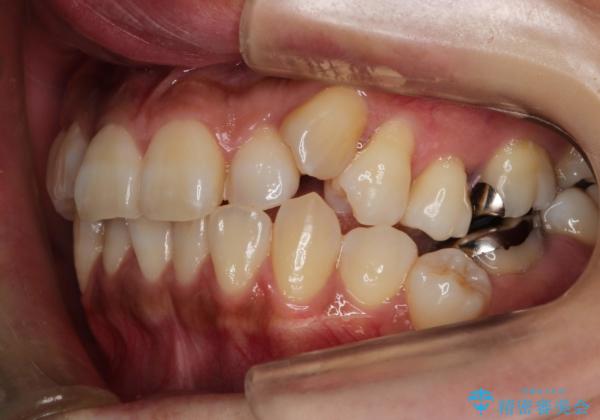

ハーフリンガル抜歯矯正 八重歯を改善する

- 30代女性

- ハーフリンガル

- 小臼歯4本抜歯によるハーフリンガル・ワイヤー矯正を計画した。

シビアな八重歯がきれいに歯列にはいることにより、笑った時の印象などもかなり大きく変わります。